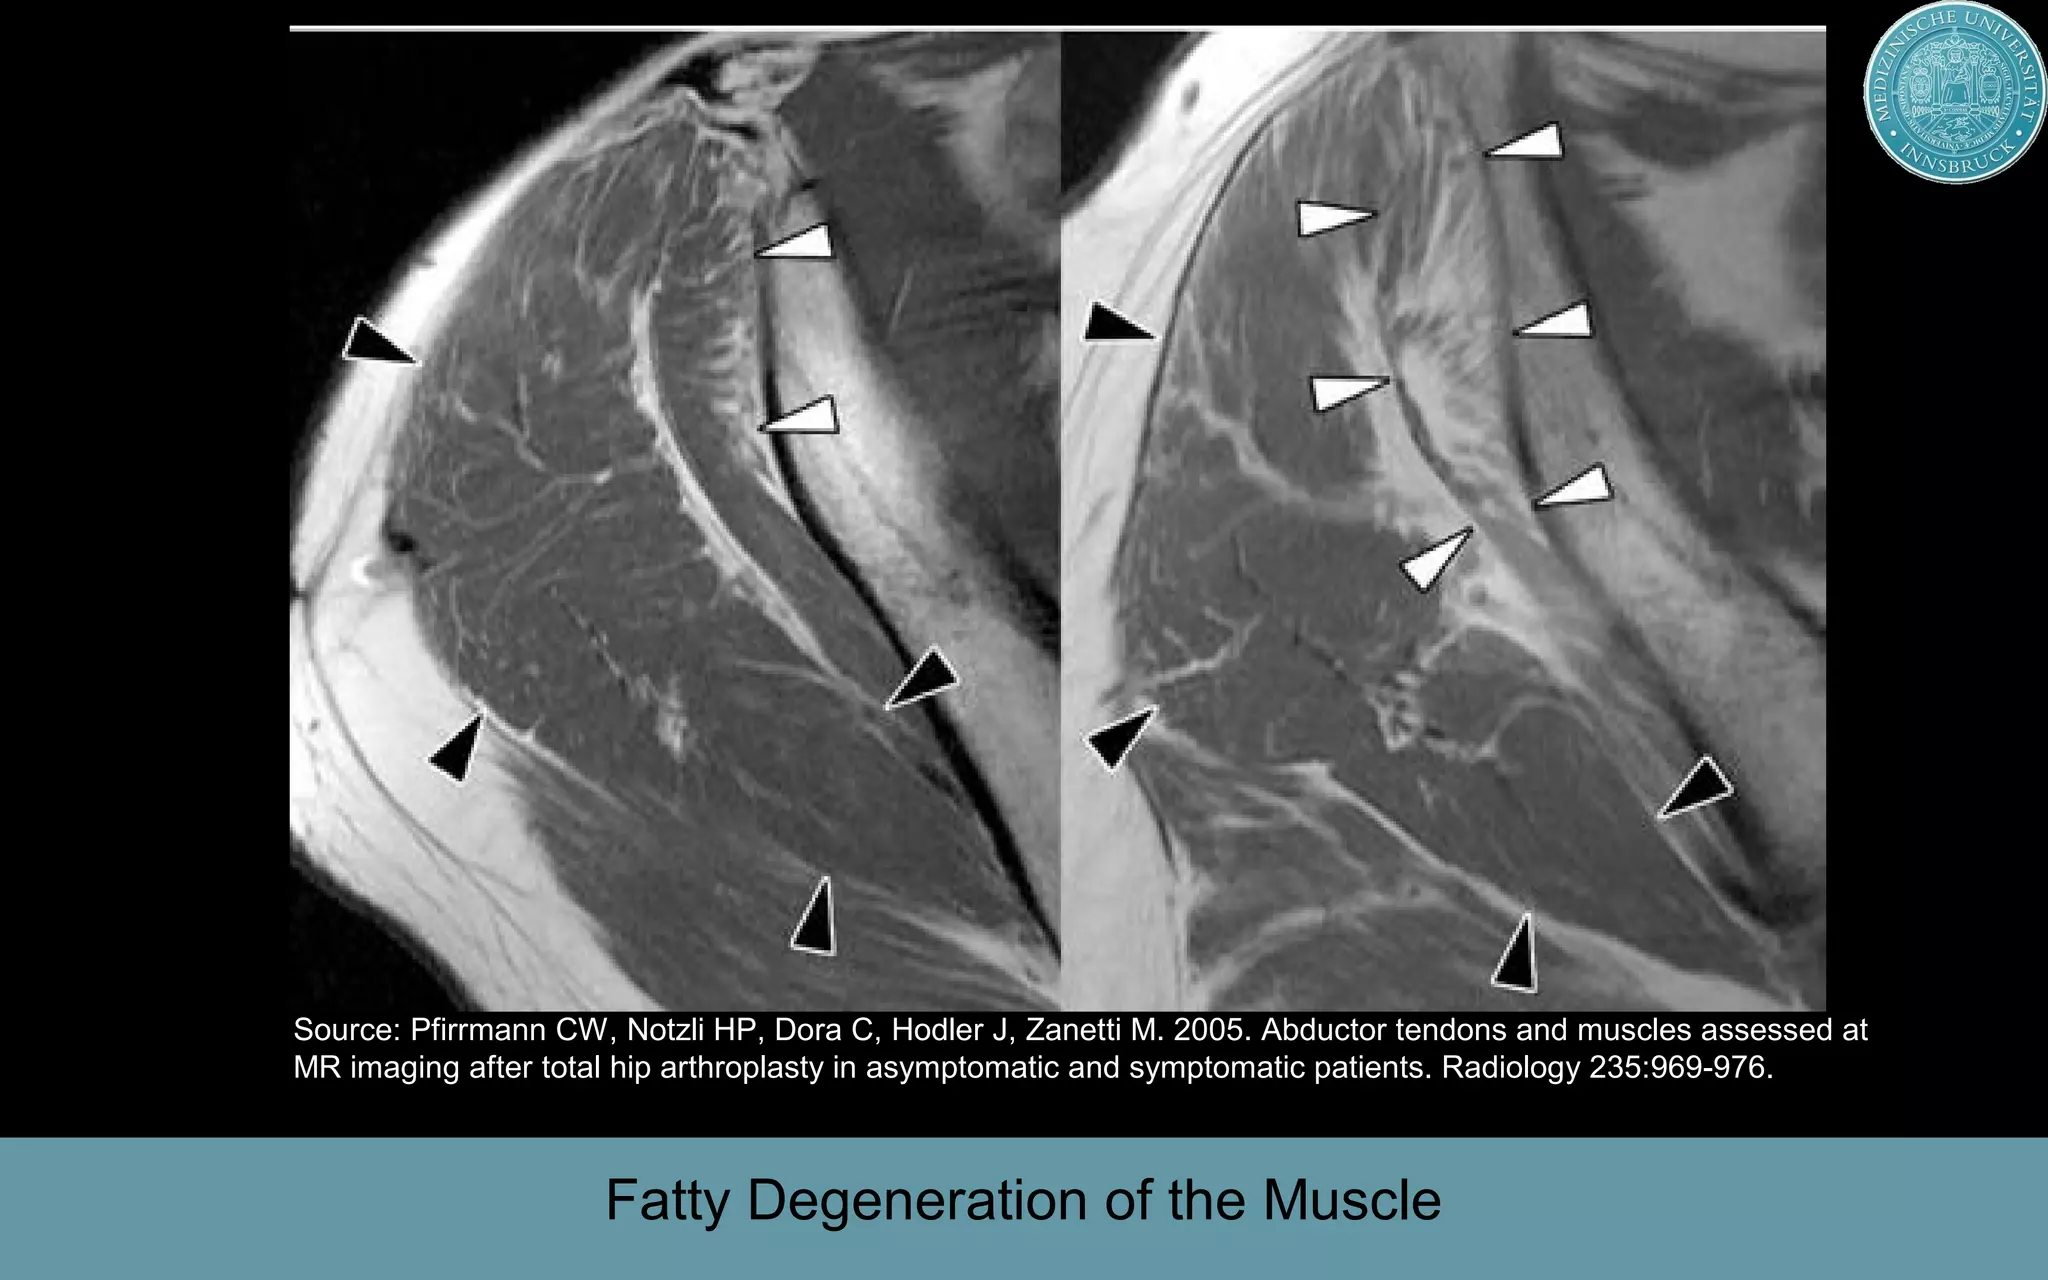

This document discusses the direct anterior approach for total hip arthroplasty. It lists advantages of the direct anterior approach such as increased stability, easier leg length equalization, lower costs by not requiring an operating table, reduced radiation exposure, faster rehabilitation, and lower risk of deep vein thrombosis. The document also discusses the historical background of the direct anterior approach, showing it has been performed since the 1880s. It presents images showing fatty degeneration of muscles and gluteal atrophy after total hip arthroplasty. Finally, it displays graphs comparing outcomes and improvements in quality of life domains between the direct anterior approach and minimally invasive approaches.